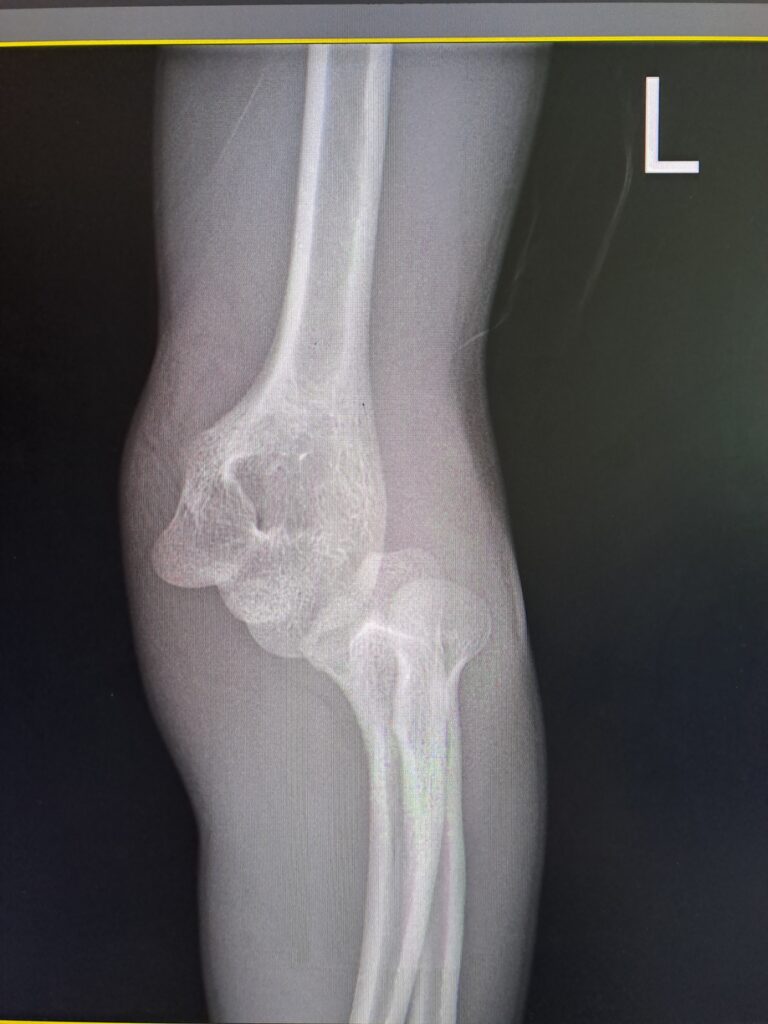

До травмпункту КНП “Вінницька обласна дитяча клінічна лікарня Вінницької обласної Ради” звернувся хлопчик 13 років із травмою лівої

верхньої кінцівки,який отримав травму внаслідок падіння.

За результатами клінічного обстеження та рентгенологічної візуалізації встановлено діагноз: закритий вивих лівого передпліччя у поєднанні з переломом медіального надвиростка лівої плечової кістки — травма, яка належить до категорії нестабільних ушкоджень ліктьового суглоба у дітей.